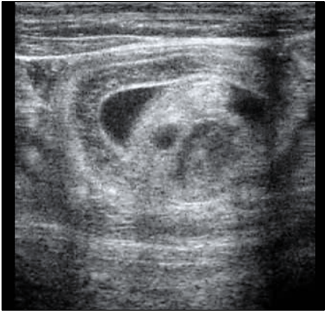

Um potro de sete meses, apresentando sinais de desconforto

e distensão abdominal progressiva, foi encaminhado ao

hospital veterinário. À avaliação ultrassonográfica registrou-se

a imagem apresentada a seguir:

Com base nos achados, qual seria a etiologia mais provável do desconforto abdominal e a indicação terapêutica mais indicada para o caso?